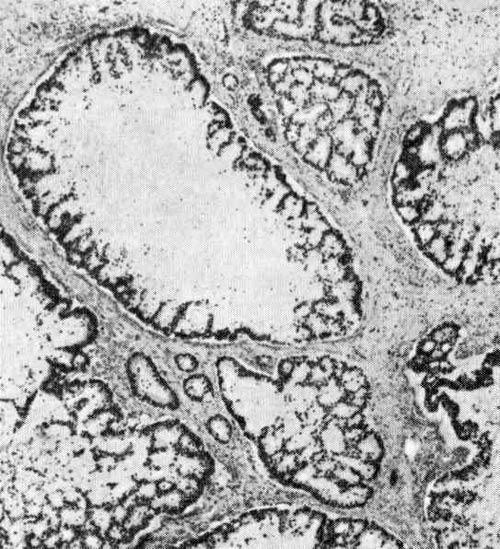

Типичная аденокарцинома толстой кишки представлена однообразными железистыми структурами с содержащими слизь эпителиальными клетками. Опухоль, как правило, высоко- или умереннодифференцирована. Низкодифференцированные или анапластические аденокарциномы встречаются редко, но если они диагностируются, морфолог должен в заключении подчеркнуть и провести дифференциальную диагностику с возможной метастатической опухолью, меланомой, карциномой пли лимфомой. «Колоректальные новообразования»,под ред. М.В.Стирнса

Этим термином обозначают аденокарциномы, секретирующие большое количество слизи. Усиленное слизеобразование чаще выявляется при аденокарциномах с типичным гистологическим строением. Согласно современным исследованиям, опухоли, в которых приблизительно 65 % клеток секретируют слизь, представлены скоплениями («озерками») слизи с очень небольшим числом эпителиальных клеточных элементов. Прогноз при муцинозных аденокарциномах менее благоприятен, чем при обычных аденокарциномах, секретирующих небольшое количество слизи. …